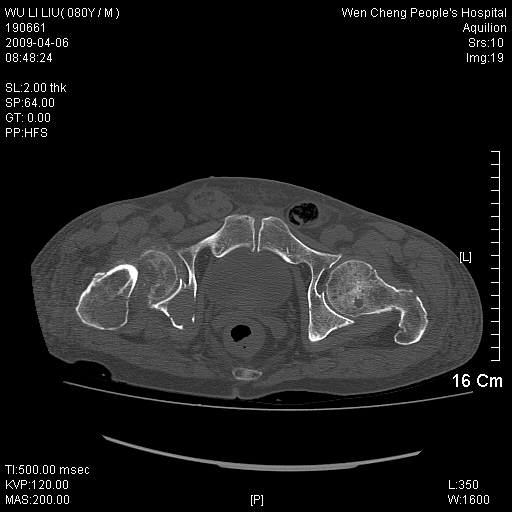

以下是引用zjzjr在2009-4-7 12:13:00的发言:[br]支持多发性转移瘤,右股骨颈骨折,腰椎亦有压缩性骨折.肝内胆管结石伴胆内外胆管扩张,左肾结石.

以下是引用liaoqiang在2009-4-7 8:44:00的发言:[br]考虑多发性骨髓瘤伴肝肺转移、肝内胆管结石、左肾结石、右股骨颈骨折。

以下是引用余辉在2009-4-7 8:52:00的发言:[br]椎骨及骨盆骨质疏松,骨破坏主要累及椎体,各骨破坏较广泛,各病灶边缘均较清晰锐利,血沉增快,白细胞增高.支持考虑多发骨髓瘤,建议查本尿周氏蛋白.[br]胆内胆管及左肾结石[br]右股骨颈骨折,考虑病理性